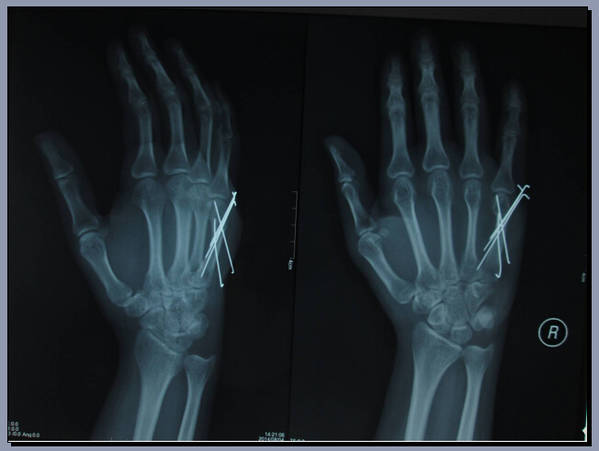

手外科会议带去一个讨论题目